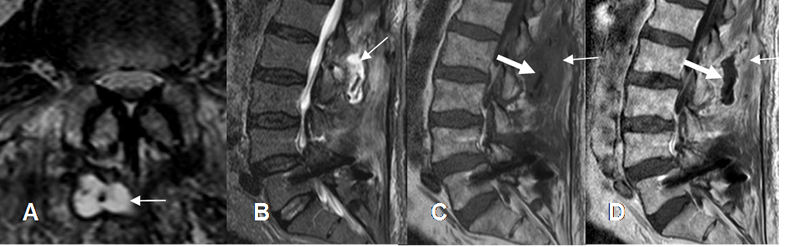

Infección:

Se puede desarrollar hasta 2 años después de la intervención. La de tejidos superficiales, se manifiesta mas temprano con eritema, dolor y supuración.

Con la RM se aprecia colección líquida y realce del contraste en los tejidos blandos. Puede existir un tracto de fistulización y empiemas epidurales. (30). (Fig 130).

Fig 130. Infección postQx.

A: RM axial y B: RM sagital en T2. Cambios postQx, con colección hiperintensa en los tejidos blandos.

C: RM sagital en T1 y D: RM sagital en T1 con contraste. Cambios inflamatorios de tejidos blandos, hipointensos y que realzan con el contraste (Flecha delgada). La colección no realza y corresponde a absceso. (Flecha gruesa).